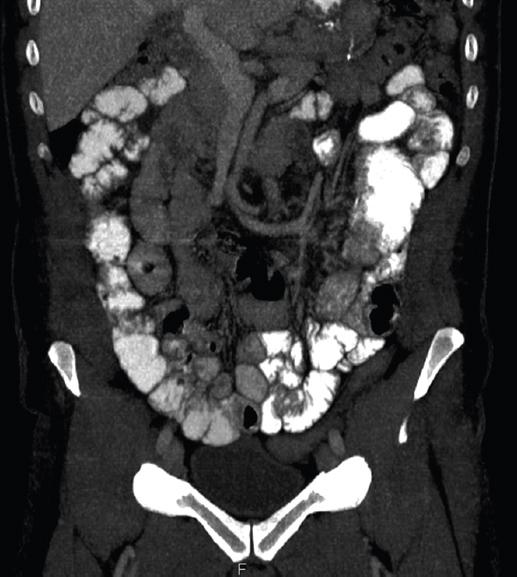

A la exploración, el paciente se encontraba en postura antiálgica, con un abdomen doloroso a la palpación en el mesogastrio, sin distensión ni signos de irritación peritoneal. En la analítica sanguínea se apreciaba neutrofilia (78.5%) sin leucocitosis ni otras alteraciones. Se realizó una tomografía computarizada (TC) de abdomen-pelvis con contraste intravenoso en la que, a nivel del pie de asa, se identificó una angulación y una disminución de calibre de un segmento de intestino delgado en el hipocondrio izquierdo (Fig. 1), junto a signos indirectos de hernia interna, como el «arremolinamiento» de los vasos del meso (Fig. 2). Se practicó una laparoscopia exploradora urgente, en la que se halló una herniación de la casi totalidad del asa alimentaria a través del ojal mesentérico de Petersen (Fig. 3) y un ojal mesentérico del pie de asa de mediano tamaño (Fig. 4). Se realizó reducción del segmento de asa herniado y cierre del ojal con sutura barbada de polipropileno 2/0, y cierre del ojal mesentérico del pie de asa con la misma sutura.

Figura 2 Tomografía computarizada abdomino-pélvica con contraste intravenoso (corte coronal) en la que se evidencia rotación de los vasos mesentéricos en sentido antihorario, lo que junto a los hallazgos de la figura 1 sugiere la existencia de una hernia interna.